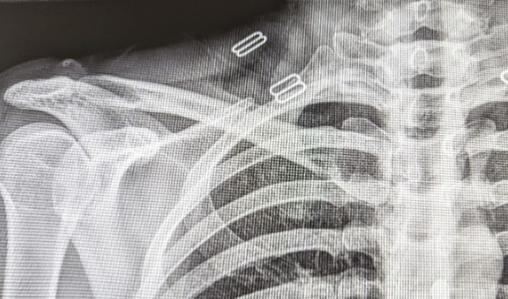

Sur la radiographie (fig. 1 ), aucune lésion osseuse traumatique n’est constatée ; les alignements sont respectés.

Sur la radiographie (